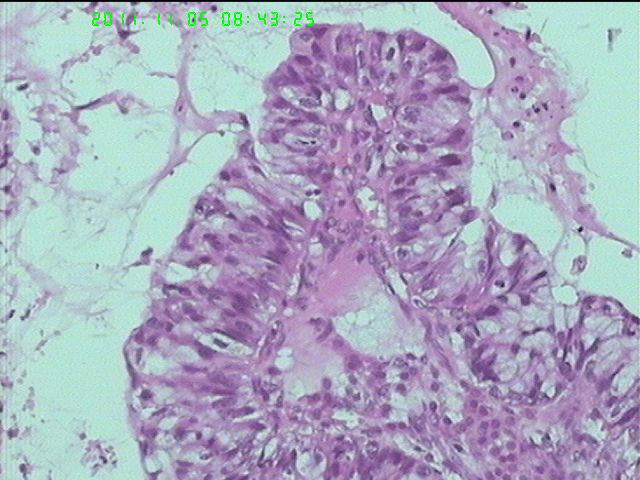

一个很有意思的病例

37岁女性患者,左卵巢肿块术中快速:恶性。术后左卵巢囊实性肿块14*9*5CM,灰黄色,部分乳头状,粘液样外观;子宫内膜厚1.5CM;网膜见多个小结节。图1--14左卵巢  15-19网膜  20--23宫腔

图1、4、5、6、11中可见疏松组织,网状结构,并见可疑透明小体,加上患者年纪较年轻,卵黄囊瘤不能除外,粘液腺结构可能是卵黄囊中的内胚层成分。且形态上与网膜结节相似。

请临床查有无阑尾病变,排除阑尾肿瘤转移后,如果没有明确浸润,倾向粘液性*交界性肿瘤伴腹膜种植,肠型。

总之先排除阑尾来源,再看有无浸润,有浸润才打癌。

左卵巢黏液性腺癌伴内膜网膜转移.